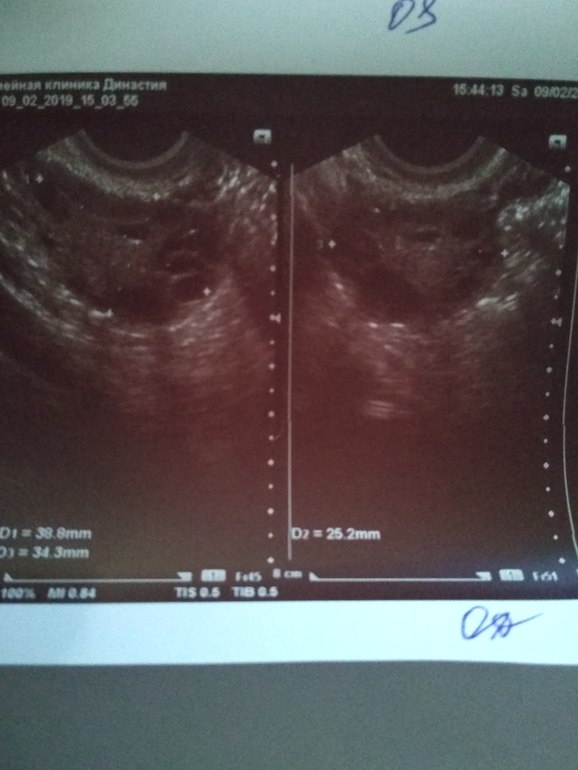

9.02.19 18 ДЦ - 36,6 ( в этот день не выдержала пошла на фолликулометрию...,там мне сказали,что овуляция у меня была...когда непонятно...делала тесты на овуляцию 2 полоска была призрачная...делала тесты с 4.02.19 по 8.02.19 как положено по инструкции. По фолликулометрии вот что сказали: Эндометрий 5 мм однородный,повышенной эхогенности..., в левом яичнике кистозное желтое тело 18*14 мм со слабым кровотоком по периферии (врач узист сказал,что в желтом теле есть немного крови...я ее спросила почему так?? Она толком не ответила,сказала типа нечего страшного так бывает...)., свободная жидкость в позадиматочном пространстве: "следы" жидкости.,ЗАКЛЮЧЕНИЕ: несоответствие эндометрия дню цикла. Овуляторный цикл. Мультифолликулярная эхоструктура яичников.)

Жёлтое тело в левом яичнике